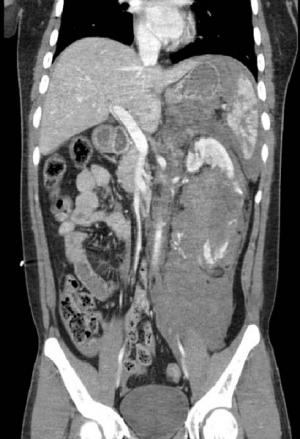

20대 중국인 교통사고로 중상…권역외상센터서 치료응급실 빠른 전원 결정 및 의료진 합진으로 목숨 구해사고 예방 위한 제도적 개선 물론 안전의식 제고 절실 △22분만에 이송 결정코리안 드림을 꿈꾸며 제주에서 일자리를 찾은 외국인 청년 상하이씨(26·가명)는 지난해 겨울 승용차를 타고 출근하던 중 차량이 전복되는 사고를 당했다.당시 119 구급대에 의해 상하이씨가 서귀포시내 병원으로 이송된 시각은 오전 8시13분. 해당 병원 응급실은 혈복강이 의심됨에 따라 22분만에 상하이씨를 권역외상센터로 이송